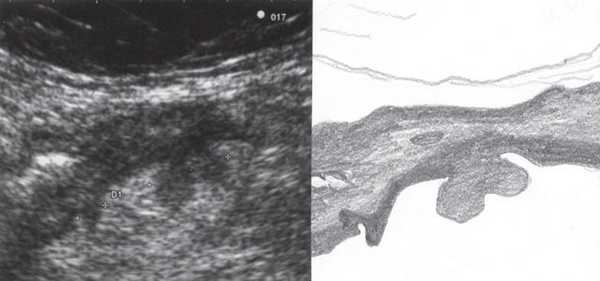

При УЗИ были выявлены диффузные изменения печени и поджелудочной железы, признаки хронического бескаменного холецистита, ангиомиолипома левой почки (без динамики за несколько лет), состояние после экстирпации матки с придатками. В левой подвздошной области соответственно зоне максимальной пальпаторной болезненности на протяжении 9 см отмечалось утолщение стенок толстой кишки до 6-7 мм (рис. 1). Перистальтика кишки отсутствовала, гаустрация была слабо выражена, при этом визуализировалось несколько болезненных при надавливании датчиком выпячиваний пониженной эхогенности, размером от 7 до 20 мм (рис. 2, а, б) с тонкой стенкой до 0,9-1,1 мм и наличием в некоторых из них фрагментов кишечного содержимого и газа (рис. 3, а, б).

Рис. 2. Эхографическая картина дивертикулита. Трансабдоминальное исследование линейным датчиком 7,5 МГц.

а) Продольный срез.

б) Поперечный срез.

В приведенном наблюдении при УЗИ визуализировались множественные выпячивания истонченной кишечной стенки. На участках утолщенной стенки между дивертикулами и в самих дивертикулах сосудистый рисунок был обеднен или не визуализировался, что подтверждает роль сосудистого фактора в развитии болезни: сдавление внутристеночных сосудов с нарушением микроциркуляции, наличие ишемии и замедления венозного оттока. Некоторые дивертикулы были заполнены гомогенным аваскулярным содержимым средней эхогенности, без признаков внутрипросветного движения, так что содержимое сливалось с изображением стенки. В других дивертикулах пузырьки газа, выступая в качестве естественного контраста, позволили детально рассмотреть истонченную до 0,9-1,1 мм стенку кишки, лишенную гипоэхогенного мышечного слоя. Форма этих дивертикулов приближалась к шаровидной, устье было меньше, чем диаметр дивертикула. Однако встречались и выпячивания в форме конусов, с устьями, превышающими размеры самого дивертикула, в них прослеживалось продолжение гипоэхогенного мышечного слоя стенки.

Очевидно, эта разница в ультразвуковом изображении дивертикулов отражает стадии их формирования: округлые с истонченной стенкой и отсутствием в ней мышечного слоя - это сформированные дивертикулы, в то время как другие, в которых еще прослеживается мышечный слой или его фрагменты, - дивертикулы на стадии формирования.